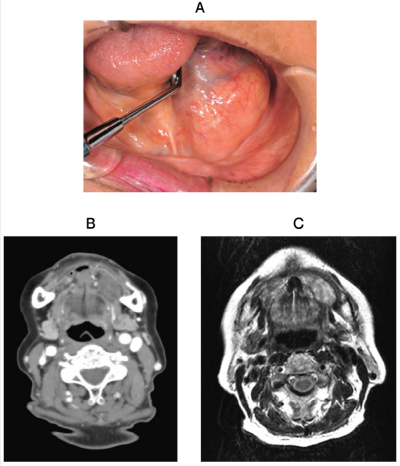

75歳の女性。左側口底の腫瘤を主訴として来院した。5か月前に気付いたが、疼痛がないためそのままにしていたという。初診時の口腔内写真、CT、MRI T2 強調像及び生検時の H-E 染色病理組織像を別に示す。